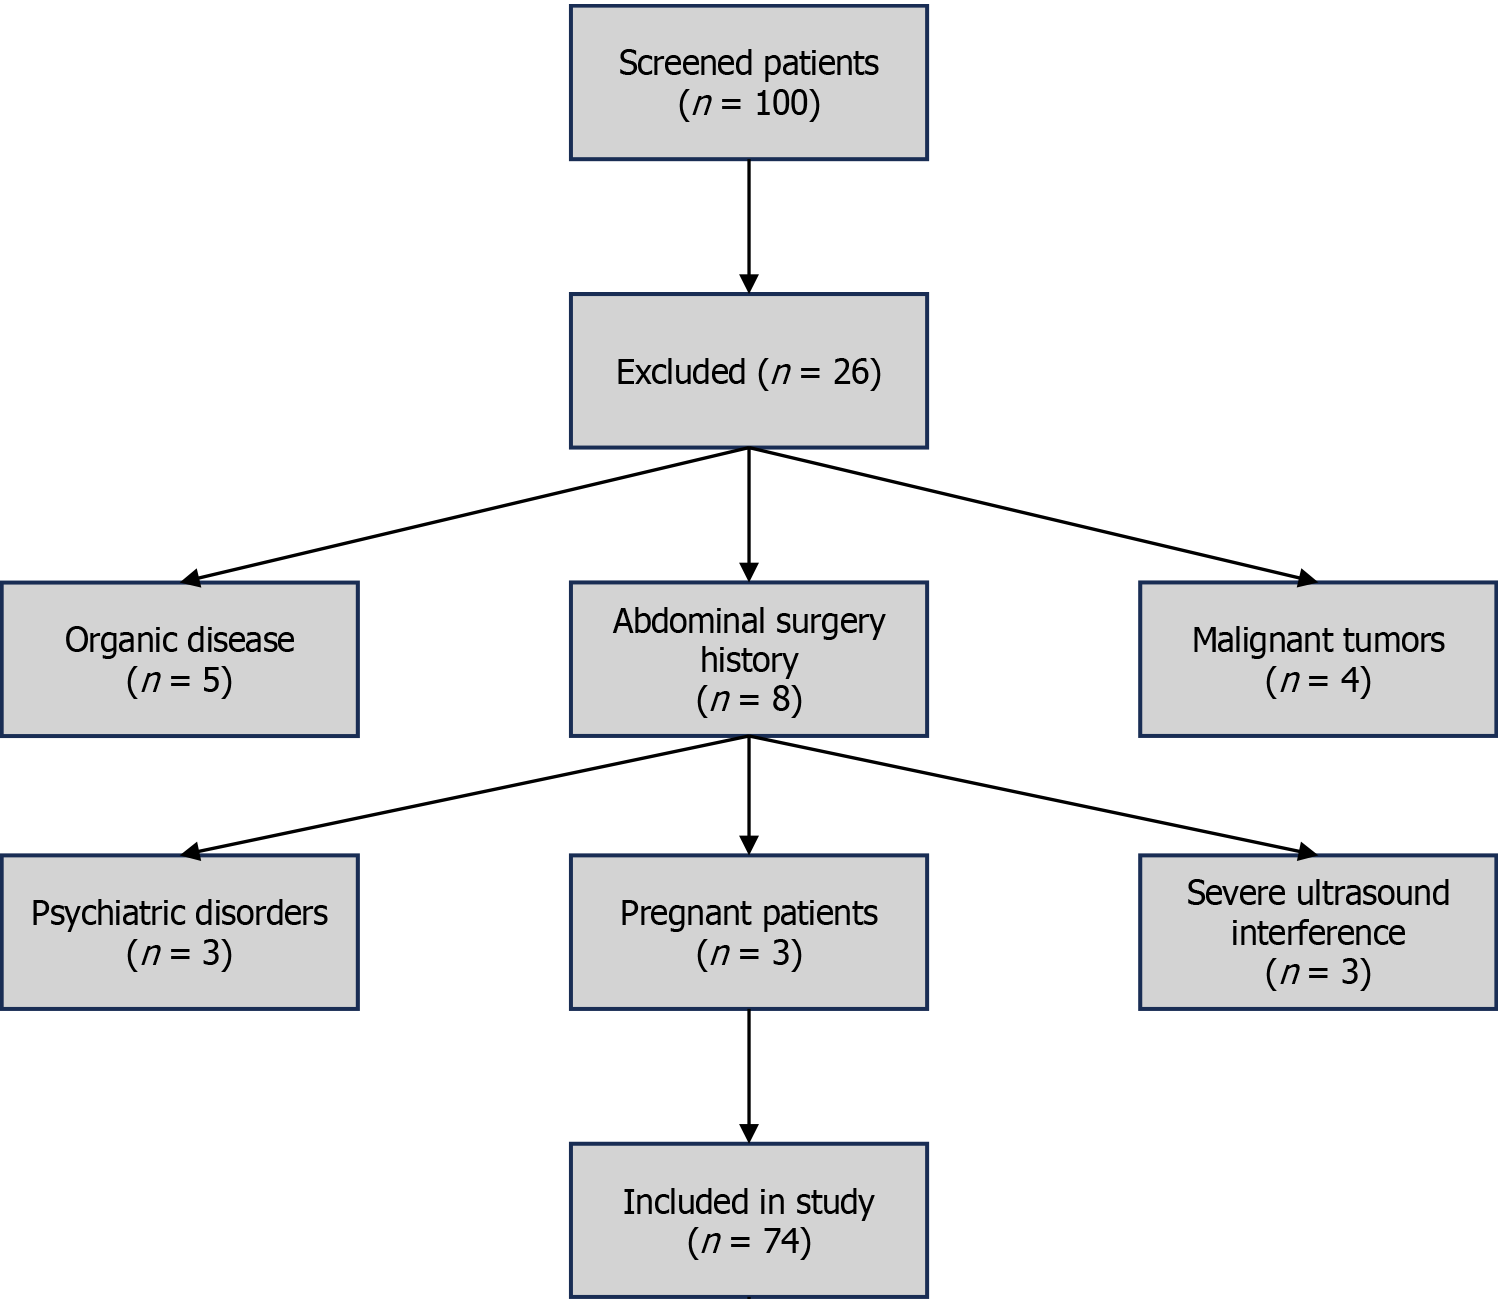

From July 2022 to July 2024, our hospital screened a total of 100 patients suspected of acute appendicitis, including 53 men and 47 women, aged between 18-70 years, with a mean age of 44.72 ± 8.16 years (see Figure 1). The body mass index ranged from 18-26 kg/m², with a mean body mass index value of 22.12 ± 1.54 kg/m2. Those patients who met the following criteria were included in the present study: (1) Age ≥ 18 years old; (2) Accompanied by upper abdominal pain, nausea and vomiting, consistent with the clinical manifestations of acute appendicitis; (3) Can tolerate abdominal ultrasonographic examination and was able to cooperate with the examination process; and (4) The clinical data of the patient were complete, including medical history, laboratory tests, imaging examination results, and surgical/pathological follow-up. A total of 26 patients did not meet the inclusion criteria, the exclusion criteria were as follows: (1) Patients with organic disease (n = 5), namely, patients with severe cardiovascular disease (such as congestive heart failure), severe liver and kidney dysfunction (such as end-stage renal disease), diabetes, and ketoacidosis which affected the reliability of disease judgment and study data; (2) A history of abdominal trauma or surgery (n = 8) including open surgery and laparoscopic surgery (due to possible formation of abdominal adhesions after surgery that affected the interpretation of ultrasonographic imaging); (3) Patients with malignant tumors (n = 4): Including previously or currently diagnosed gastrointestinal tumors and pelvic malignant tumors, in order to avoid interference with ultrasonographic examination results owing to these lesions; (4) Psychiatric patients (n = 3): Including those diagnosed with schizophrenia, bipolar disorder, and severe depression who may not have been able to accurately express symptoms or cooperate with examinations; (5) Pregnant patients (n = 3): Pregnant women who may exhibit physiological abdominal changes, such as uterine enlargement leading to changes in the position of the appendix, which would affect the accuracy of ultrasonography imaging; and (6) Serious ultrasonography interference factors (n = 3): Including severe intestinal distension, and ascites that may have led to poor ultrasonographic image quality and resulted in an inability to obtain reliable imaging data.